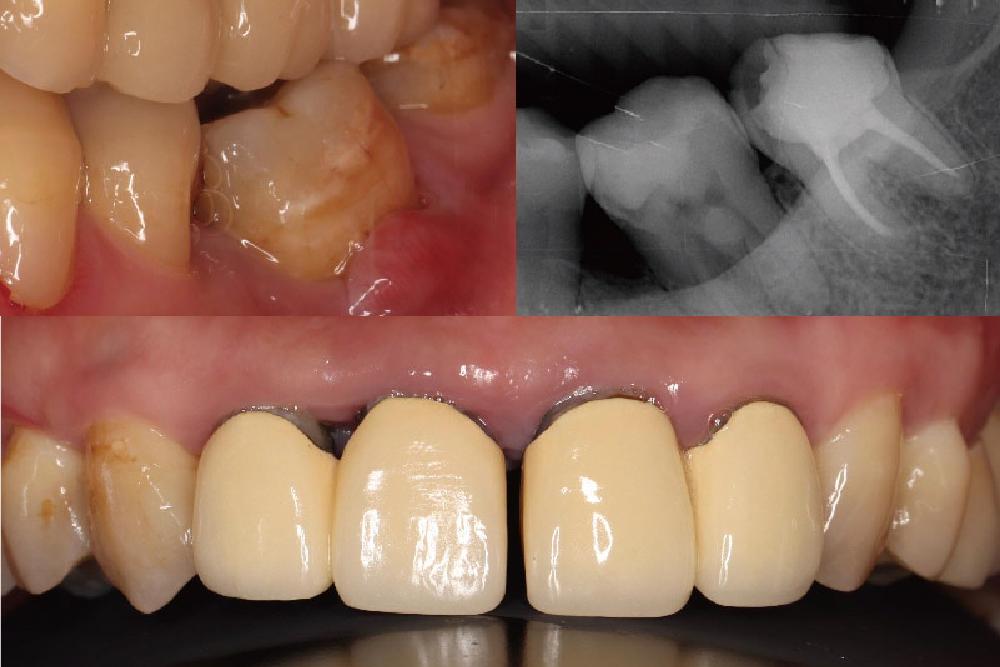

當代牙科醫療體系牙周病暨植牙專科醫師葉立維表示,經過環口式全口X 光片和牙神經活性檢查後,發現患者左邊下面臼齒曾有大範圍填補,同時牙神經也沒有活性反應,顯示這顆牙齒同時有牙髓和牙周的問題;再加上此區域的齒槽骨已經流失 50%以上,診斷為全口中度至嚴重牙周病,完整檢查與精確診斷後擬定了全口治療計畫。

經過牙周特別檢查,加上測量囊袋深度和 X 光片上顯示齒槽骨流失的狀況,可以估計整體或單獨牙齒的預後。醫師表示,患者的治療計畫包括顯微根管治療後,用覆蓋式全瓷嵌體修復左下大臼齒的牙髓和牙周問題、全口牙周病治療、拆除前牙區不密合的假牙並且重建,同時針對右下缺牙區域因拔牙很久導致牙齦萎縮,先以游離牙齦移植術增寬牙齦後,再進行人工植牙療程。